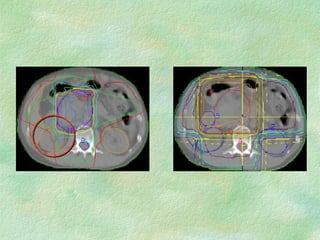

Virtual Simulation: -  Immobilization CT Coordinate system Structure Delineation Isocentre localization Beam placement/definition

Problems: Images are static and organ motion is not evident Correlation of imager/patient/treatment coordinate systems is non-trivial - DRRs Resolution of data set is limited by slice thickness - structure definition/DRR Imaging modality - image fusion

Problems: Images arestatic and organ motion is not evident Correlation of imager/patient/treatment coordinate systems is non-trivial - DRRs Resolution of data set is limited by slice thickness - structure definition/DRR Imaging modality - image fusion